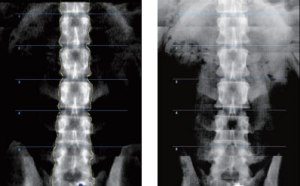

‘InAlyzer AIR’ is the DXA (Dual energy X-ray Absorptiometry) based on 64 channels true fan beam technology and it is the latest medical device applying the latest reference data. It is the first bone densitometry in Korea that provides DR images through high-resolution data processing technology and supports optimal diagnosis through accurate ROI (Region Of Interest) selection. Although bone densitometry is not an imaging diagnosis device, InAlyzer

AIR provides the DR imaging that can greatly support physicians in subjective diagnosis as well as setting up accurate ROI.